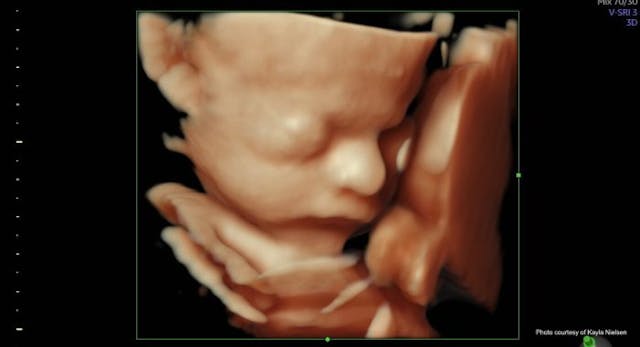

Extreme mental struggles surfaced in the first trimester—turmoil so unlike the pregnancies with the boys. And joy erupted at the anatomy scan as we heard, “It’s a girl!” like music to our ears. But I was no rookie. Something felt off about the silence of the sonographer. I pushed the uneasy feeling aside.

Just like that, we made for a bigger city — the end goal to undergo fetal surgery. Laurel’s back would be repaired while she was still in the womb. We met a team of professionals, receiving a crash course in these complex conditions. We were even starting to “get used to” the idea of them.

Scans were frequent now, and due to an enlarged head size, they decided Laurel had to come early. At 33 weeks — the same number of years Jesus walked this earth — Laurel Rose was delivered via C-section.